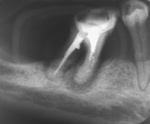

Ryc. 1. Ząb 47 zakwalifikowany do ekstrakcji. Reendodoncja i zabiegi fizykalne na życzenie pacjenta. RTG przed leczeniem.

Pacjentka zgłosiła się ze skrajnie zniszczoną strukturą kostną w okolicy okołowierzchołkowej zęba trzonowego (ryc. 1).

W korzeniu dalszym: (blisko bifurkacji) widoczna była perforacja, w okolicy okołowierzchołkowej rozrzedzenie struktury kostnej. Tylko apeks tkwił w kości żuchwy. W korzeniu bliższym widoczna duża regularna osteoliza i brak struktury kostnej. Destrukcja brzegu wyrostka zębodołowego (osteoliza brzegu kości, przy korzeniu bliższym całkowita), w obrazie klinicznym: obnażenie korzeni z widoczną bifurkacją, rozchwianie III st., kamień nazębny. Pacjentka nie wyraziła zgody na usunięcie zęba. Przyjęła propozycję ponownego leczenia endodontycznego oraz zabiegów magnetostymulacji, bez nadziei i gwarancji na powodzenie terapii.